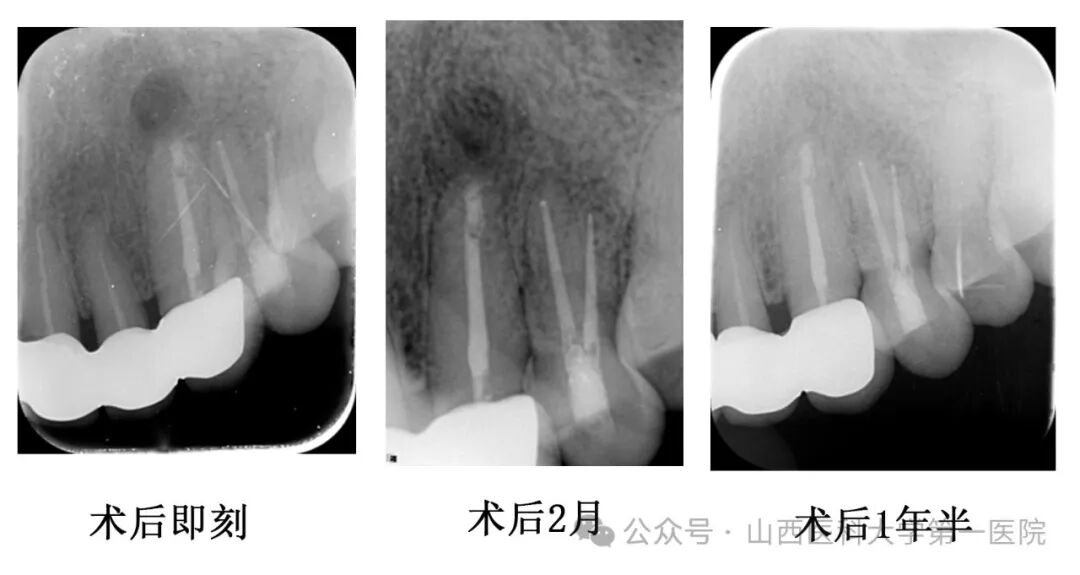

医生术中采用牙龈翻瓣术清理根尖周围感染组织,同时对患牙进行倒预备倒充填严密封闭根尖,术后定期复查发现患者牙龈红肿明显消退,根尖炎症范围逐渐减小,1年后根尖炎症完全消失,成功保留了天然牙。